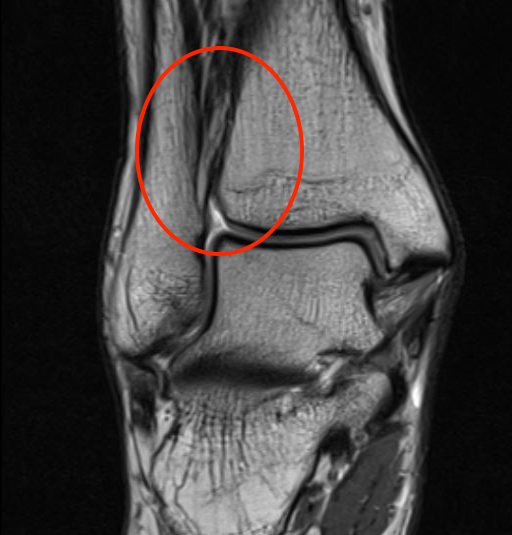

MRI

Tear of AITFL / intact PITFL

Tear of AITFL, intact PITFL, and syndesmotic injury with external rotation of the fibula

Tear of AITFL & PITFL with syndesmotic widening